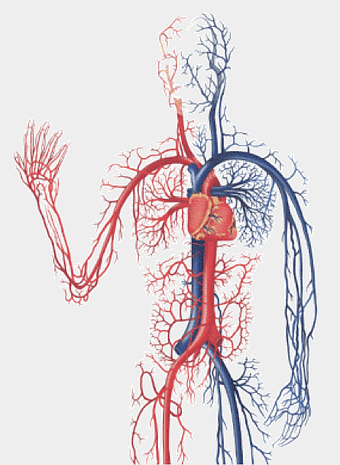

red vascular network illustration, blood vessel line art, human body circulatory system, thrombus medical graphic, anatomical red vein depiction, cardiovascular disease diagram, artery and vein branching++) -

human circulatory system diagram, blood vessel network illustration, human anatomy chart, cardiovascular system overview, human body medical illustration, physiological system depiction, organ function visualization -